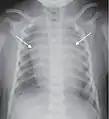

Chest film showing increased opacity in both lungs, indicative of pneumonia